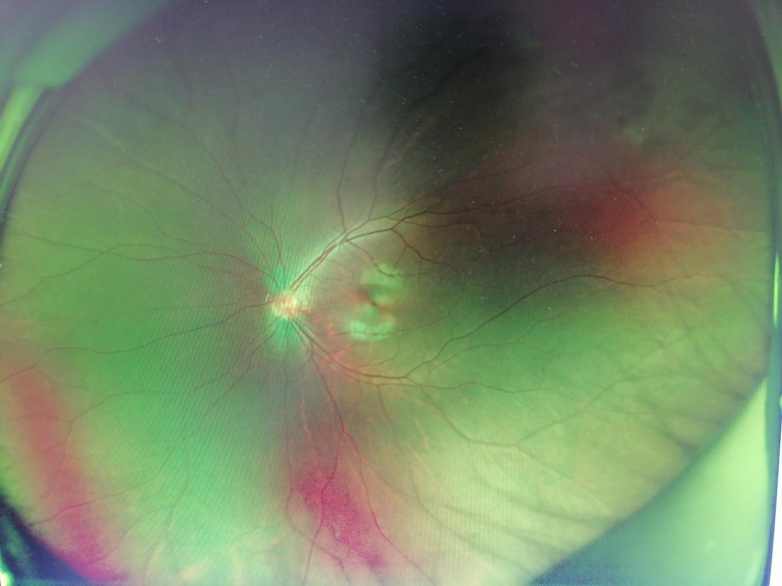

眼底照相检查结果显示,小张左眼颞上方周边部存在视网膜病变。为确保诊疗精准,周医生第一时间将小张转诊至南昌爱尔眼科医院眼底病科会诊,眼底病科赖梦云医生接诊后,立即为小张左眼进行散瞳检查,进一步明确病情。经详细检查发现,小张左眼颞上方玻璃体增殖牵拉视网膜,最终确诊为左眼视网膜变性。为避免眼底病变进一步发展,防止视网膜脱离等严重后果,赖梦云医生建议为小张实施左眼视网膜激光光凝治疗,小张父母听从专业建议,同意接受该治疗。